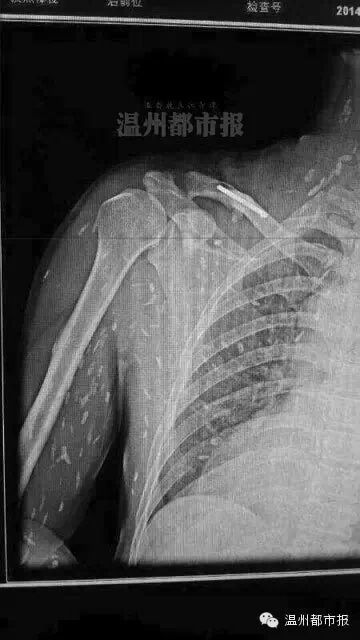

网络流传的满是寄生虫的X光片照片。图片来自网络

这两天,一张布满白点、看起来像长满寄生虫的图在网上热传。配图文字称:“瑞安一病人爱吃生鱼片,满身寄生虫?”

一位名为“doctor吴”的网友,在一论坛上发表了一篇《对微信流行的寄生虫一事个人见解》。文中,“doctor吴”表示,他从医学角度上对该片持怀疑态度。他认为,寄生虫的密度跟人体密度相仿,简单普通的X光并不能让它显影,CT下基本不能看到,除非聚集成团或者蛔虫。因为在胆道中,胆汁密度比虫体低,虫体密度与胆管相若,CT显影为胆道堵塞。

与此同时,他还提到,如果虫体死亡后钙化,那是可以在X光片中显影的。

这一说法得到我市寄生虫学专家认可。温州医科大学基础医学院副教授、寄生虫学教研室副主任黄慧聪认为,看到这样一张X光片,假如片子本身是真实的,通常会认为是寄生虫的软组织虫体广泛分布的皮下肌肉的钙化病灶。“通俗点说,就是寄生虫在体内死亡后钙化留下的斑点。”

黄慧聪指出,活的寄生虫是游走不定的,很难被X光片拍到,在直接影像学上是看不出来的。一般是形成虫囊或钙化后才容易被X光片观察到。但形成虫囊或钙化需要较长时间,通常要半年以上。如果像网上传的那样,由于食用生食短时间内出现这样的钙化灶,这种说法是值得怀疑的。

此外,他还说,出现图片所示那样广泛分布的钙化灶,通常考虑是旋毛虫病。这可能是生吃肉类导致,通过吃鱼感染的极为罕见。假如不是旋毛虫病,也可能是肺吸虫病。后者一般是通过生食溪蟹、蝲蛄(俗称小龙虾)等感染的,患病后虫体可能会游走,像图片里显示的这么密集,他还是第一次看到。

多位医学专业人士指出,单从这张X光片上看,图中白点如果真是寄生虫钙化后的显影,很像是囊尾蚴,这是扁形动物门绦虫纲幼虫的一种类型。

由于图片原始出处很难查找,这张令人毛骨悚然的X光片真伪难辨。相关人士分析指出,一者不能排除这张照片经过PS修改伪造的可能性,二者即使照片是真的,图中的白色斑点也有可能是患者体外衣物上或躯体表面的附着物。